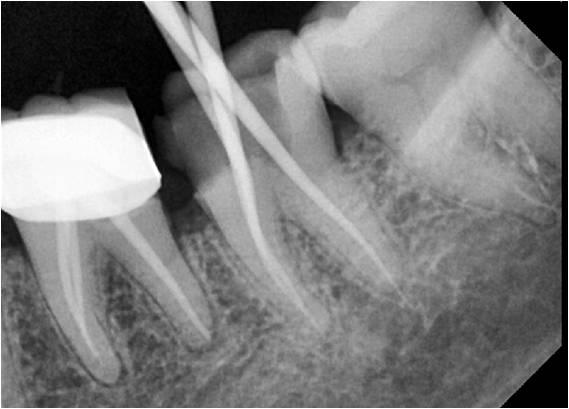

Single Sitting Rotary Root Canal System

Efficient treatment in one visit.

Reduces discomfort

Advanced technology used

Highly successful outcomes